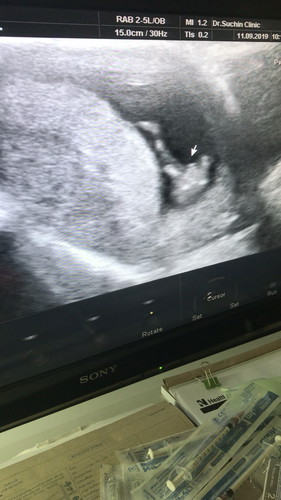

ใครพอดูรูปซาวด์เก่งๆบ้างคะช่วยดูหน่อยค่ะ

พอจะดูออกมั้ย ช หรือ ญ

เหมือนจะ ญ เลยค่ะ เพราะบ้านนี้ได้ ช จู๋จะยื่นออกมาเลยค่ะ

น่าจะ ผช. นะคะ

หมอบอกว่ามีโอกาศเป็นชายสูง กลับบ้านมาแบบคาใจมากค่ะ หมอไม่คอนเฟริมให้หายคาใจ 😆😆